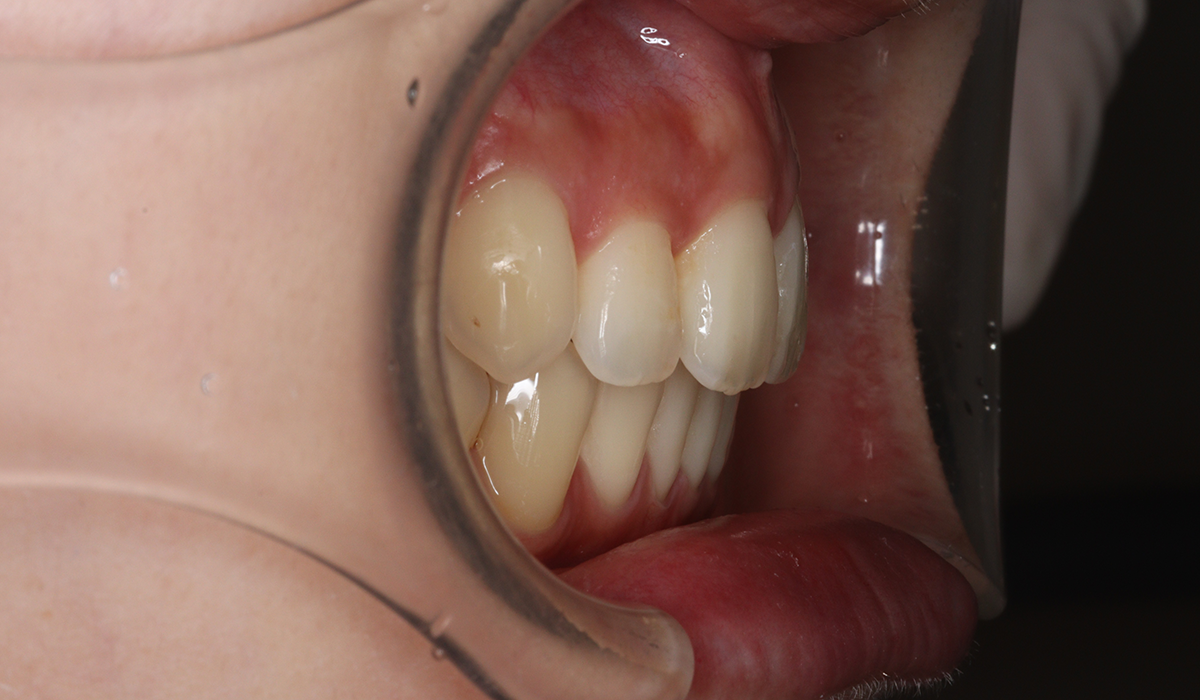

右側

術前

| 主訴 | 全体的な歯のガタツキが気になる |

| 治療内容 | 全体的な歯のガタツキを気にされており、矯正検査後叢生Ⅰ級と診断いたしました。 |